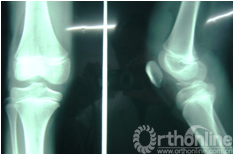

因失访12例,最终成功随访73例,随访时间10~72月,平均28.7月。末次随访时拍X线片示骨折均解剖复位或接近解剖复位;Lachman试验均为阴性;Lysholm评分94.2±3.6,较术前评分46.5±2.9有统计学意义(P<0.05)。膝关节活动度正常者64例,术后4~6周出现膝关节屈曲轻度受限者8例,活动度0°~90°,给予闭合松解后膝关节功能恢复正常;发生严重膝关节纤维化者1例,活动度0°~30°,再次行关节镜下松解后功能恢复正常。

图5 图6